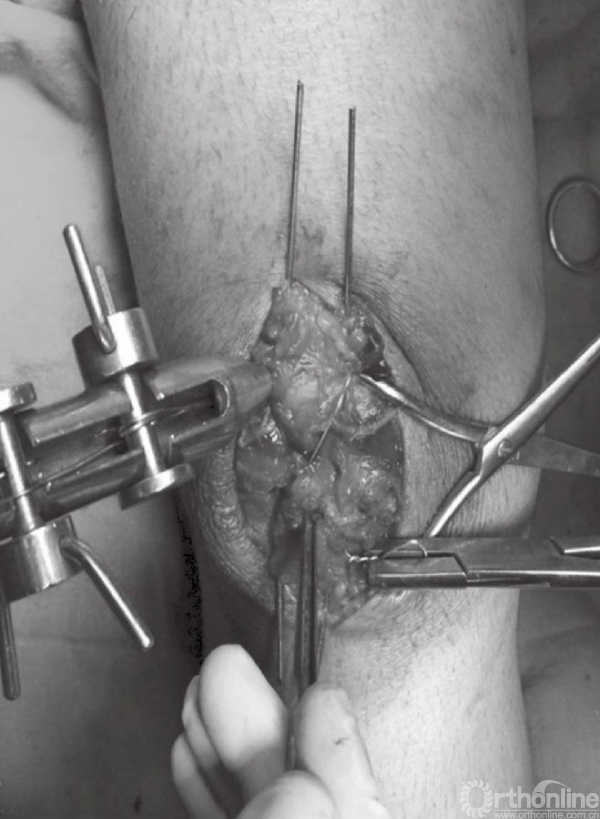

在张力带旋紧固定后,用钢丝剪剪除多余钢丝。突出的部分折弯后贴近髌骨上极放置(图15)。克氏针末端用折弯器折弯后尽量贴近髌骨表面。钢丝末端旋转后经股肌间隙埋入股四头肌腱(图16)。后期缝合肌间隙,可防止克氏针退出。克氏针远端在近髌骨处切断(图17)。用不可吸收线缝合撕裂的支持带(图18)。屈膝90°,以评估内固定的稳定性(图19)。

图15 用折弯器将克氏针近髌骨上极处折弯

图16 钢丝折弯后经肌间隙埋入股四头肌腱,这样可防止其退出

图17 在近髌骨下极处剪断钢丝

图18 在髌骨两侧用不可吸收缝线缝合撕裂的支持带

图19 屈膝90°,评估内固定的稳定性